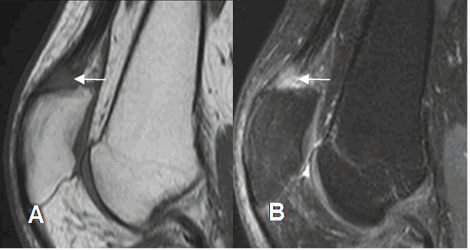

Fig 64 B. Ruptura del tendón del cuadriceps.

A: RM sagital en T2 y B: RM sagital en STIR. Solución de continuidad sobre la inserción del cuadriceps, por ruptura. Hay cambios inflamatorios en los tejidos blandos y bursitis prepatelar.